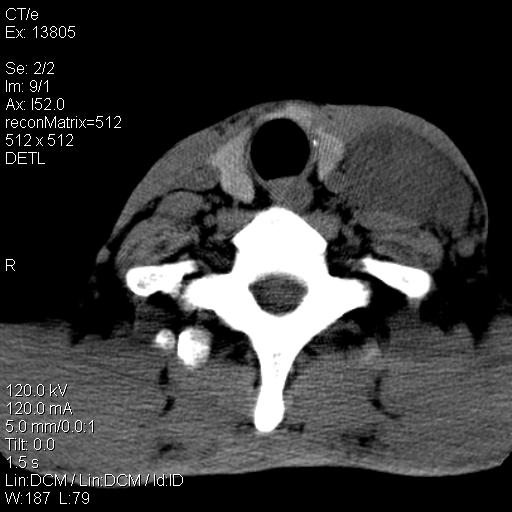

上腹部疼痛一月,呕吐10天,发现左侧颈部包快10天 胸部cr片未见明显异常。

左侧胸锁乳突肌下方、颈血管旁低密度肿块影,肿块密度尚均匀,边缘大部分清楚,邻近组织稍受压移位。考虑颈部神经鞘瘤可能性大。

颈部及腹膜后淋巴瘤可能性大